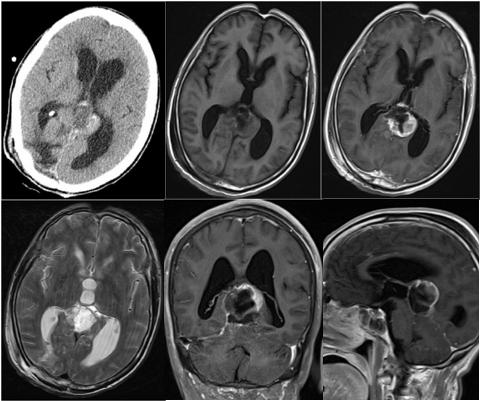

松果体区脑膜瘤一例(神经肿瘤系列十六)---浙二神外周刊(第294期)

影像总结丨脑膜三件套——脑膜瘤,hpc/sft